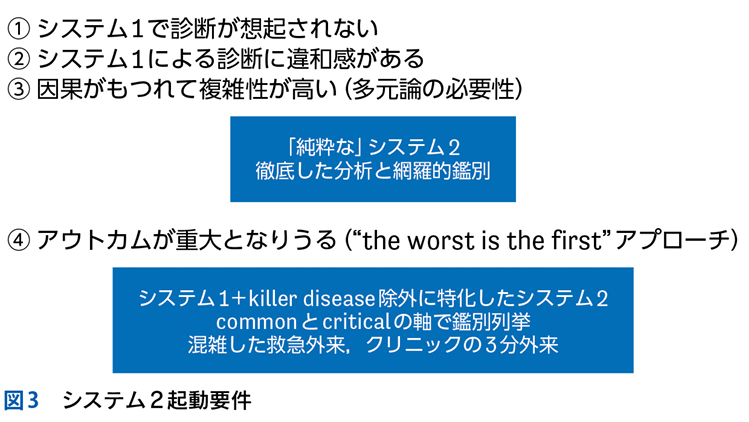

▶ システム1が使用される,短時間でのパターン認識による診断をここでは「直観的診断」,システム2に基づき,確率と論理で行われる診断を「分析的診断」と呼ぶ。

▶ 筆者の提唱する,分析的診断の「型」を図1に示した。冒頭に述べた「オリオン座を分析的に同定する手順」になぞらえ,診断推論を5つのステップにわけている。1つずつ解説しよう。